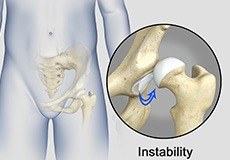

The hip joint is a “ball and socket” joint. The “ball” is the head of the femur or thighbone, and the “socket” is the cup-shaped acetabulum. The joint is surrounded by muscles, ligaments, and tendons that support and hold the bones of the joint in place. Hip dislocation occurs when the head of the femur moves out of the socket.

Hip Instability

Injury or damage to these structures can lead to a condition called hip instability when the joint becomes unstable. Hip instability can be traumatic or atraumatic. Traumatic instability can be caused by injuries from sports or motor vehicle accidents.